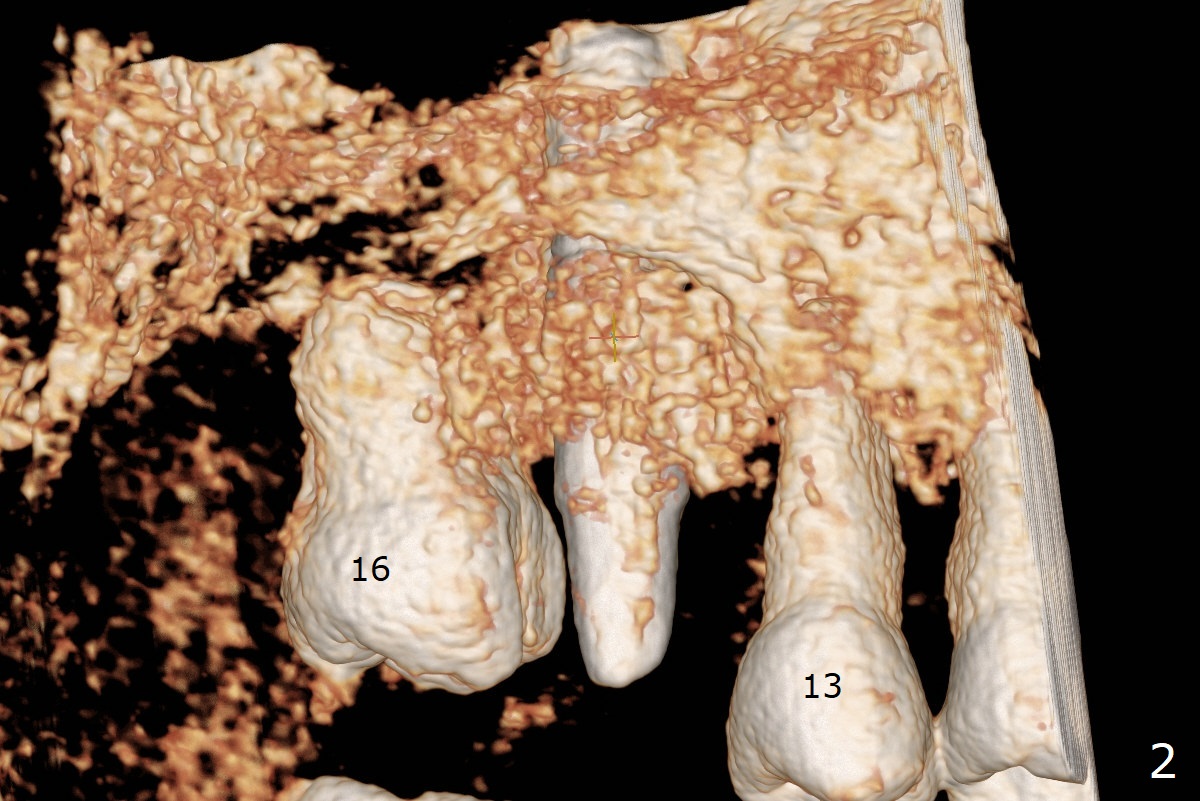

Access to the bony defect of #14 occlusally is limited due to #16 mesial incli-nation. Incision is made. After debride-ment, use of Round Brush, buccal plate decorti-cation and abutment retight-ening, sticky bone is placed around the exposure implant (I) threads and abutment (A) cuff amply (Fig.1,2 *). A piece of PRF membrane and 15x20 mm Vitala (Porcine Derived (peri-cardium) Collagen Membrane) are fixed in place around the abutment. The wound is closed with 4-0 PGA suture. The mobile teeth #12,13 and 16 are immobilized to #14 implant/abutment using acrylic as a wound dressing as well.